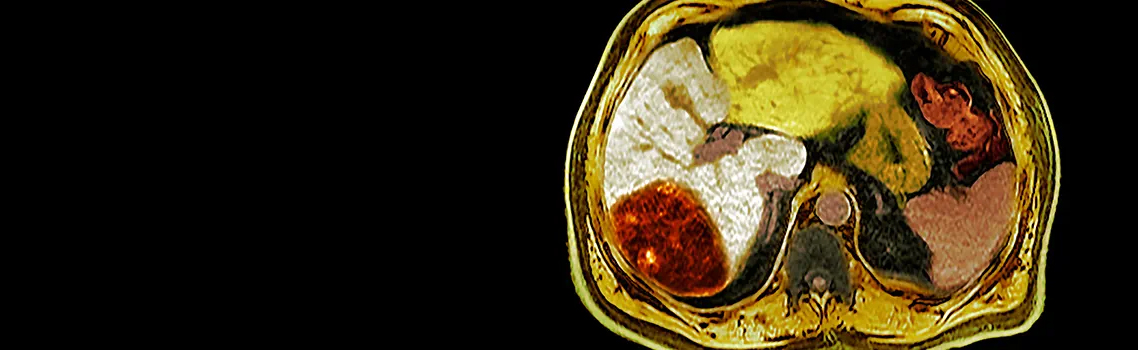

La oncología de trasplantes es un campo emergente con potencial para mejorar significativamente las tasas de supervivencia y la calidad de vida de los pacientes. En el área de la medicina donde la promesa es mayor, es en la de cáncer de hígado.

El cáncer primario de hígado es el sexto cáncer más común en el mundo y la segunda causa de muerte por cáncer, con una tasa de supervivencia de aproximadamente de apenas el 20%. Varios factores contribuyen a los desafíos terapéuticos del manejo de la enfermedad, incluida la compleja anatomía del hígado, la dificultad para detectar tumores hepáticos cuando son pequeños y operarlos cuando ya están demasiado avanzados, además, las tasas de éxito de las terapias sistémicas son relativamente bajas.

La extirpación quirúrgica es a menudo la única forma de lograr una cura, pero aproximadamente dos tercios de los tumores hepáticos se consideran inoperables. Para estos pacientes, un trasplante de hígado representa la mejor opción, o la única, que les queda.

«El trasplante de hígado es el único trasplante de órgano sólido con una eficacia notable para curar el cáncer», dice el oncólogo de trasplantes del Houston Methodist, el Dr. Maen Abdelrahim. En una revisión reciente publicada en la revista Cancers. «Al extirpar el órgano canceroso por completo y reemplazarlo con un órgano sano, podemos superar las limitaciones de las técnicas quirúrgicas actuales y aumentar la tasa de supervivencia del 20% a más del 80% para los pacientes con cáncer primario de hígado».

Para los pacientes con colangiocarcinoma intrahepático, El Hospital Houston Methodist fue el primero en informar una serie de casos prospectivos que muestra que la terapia puente neoadyuvante (quimioterapia y luego trasplante de hígado), resultó en una tasa de supervivencia a cinco años comparable a la de los pacientes con carcinoma hepatocelular que recibieron trasplantes de hígado.

El Dr. Abdelrahim analiza la evolución del campo de la oncología de trasplantes, la ampliación de los requisitos de elegibilidad, las estrategias emergentes para la terapia adyuvante y la inmunoterapia, entre otros.